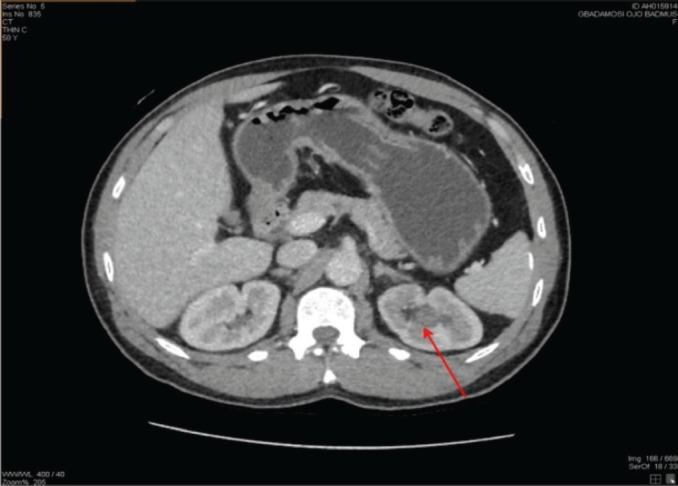

Upper urinary tract urothelial carcinomas (UTUCs) are rare malignant neoplasms, representing about 5% of all urothelial carcinomas (UCs). The incidence of primary UTUC in the renal pelvis and calyx is quite rare. UTUC is a high-grade tumour with a poor prognosis at presentation. Characteristically, UTUC presents with symptoms such as gross and microscopic hematuria or flank pain. Its mode of definitive diagnosis remains histopathology examination, despite using computed tomography urography (CTU) as the gold imaging standard. However, atypical clinical presentations and abnormal radiologic findings could lead to misdiagnosis of UTUC. We report a 59-year-old male who presented with recurrent left flank pain of 2 years duration, and an episode of hematuria. A CTU showed no classic radiologic feature of upper UCs; however, his abdominal magnetic resonance imaging was suggestive. He subsequently had a left radical nephroureterectomy. The post-operative histology report showed a primary invasive high-grade UC of the left renal pelvis and calyx. He was counseled on the findings and placed on surveillance. There are few reported cases of UTUC of the renal pelvis and renal calyx; given that it is a rare malignancy. This is quite concerning, especially with the missed imaging finding by CTU.